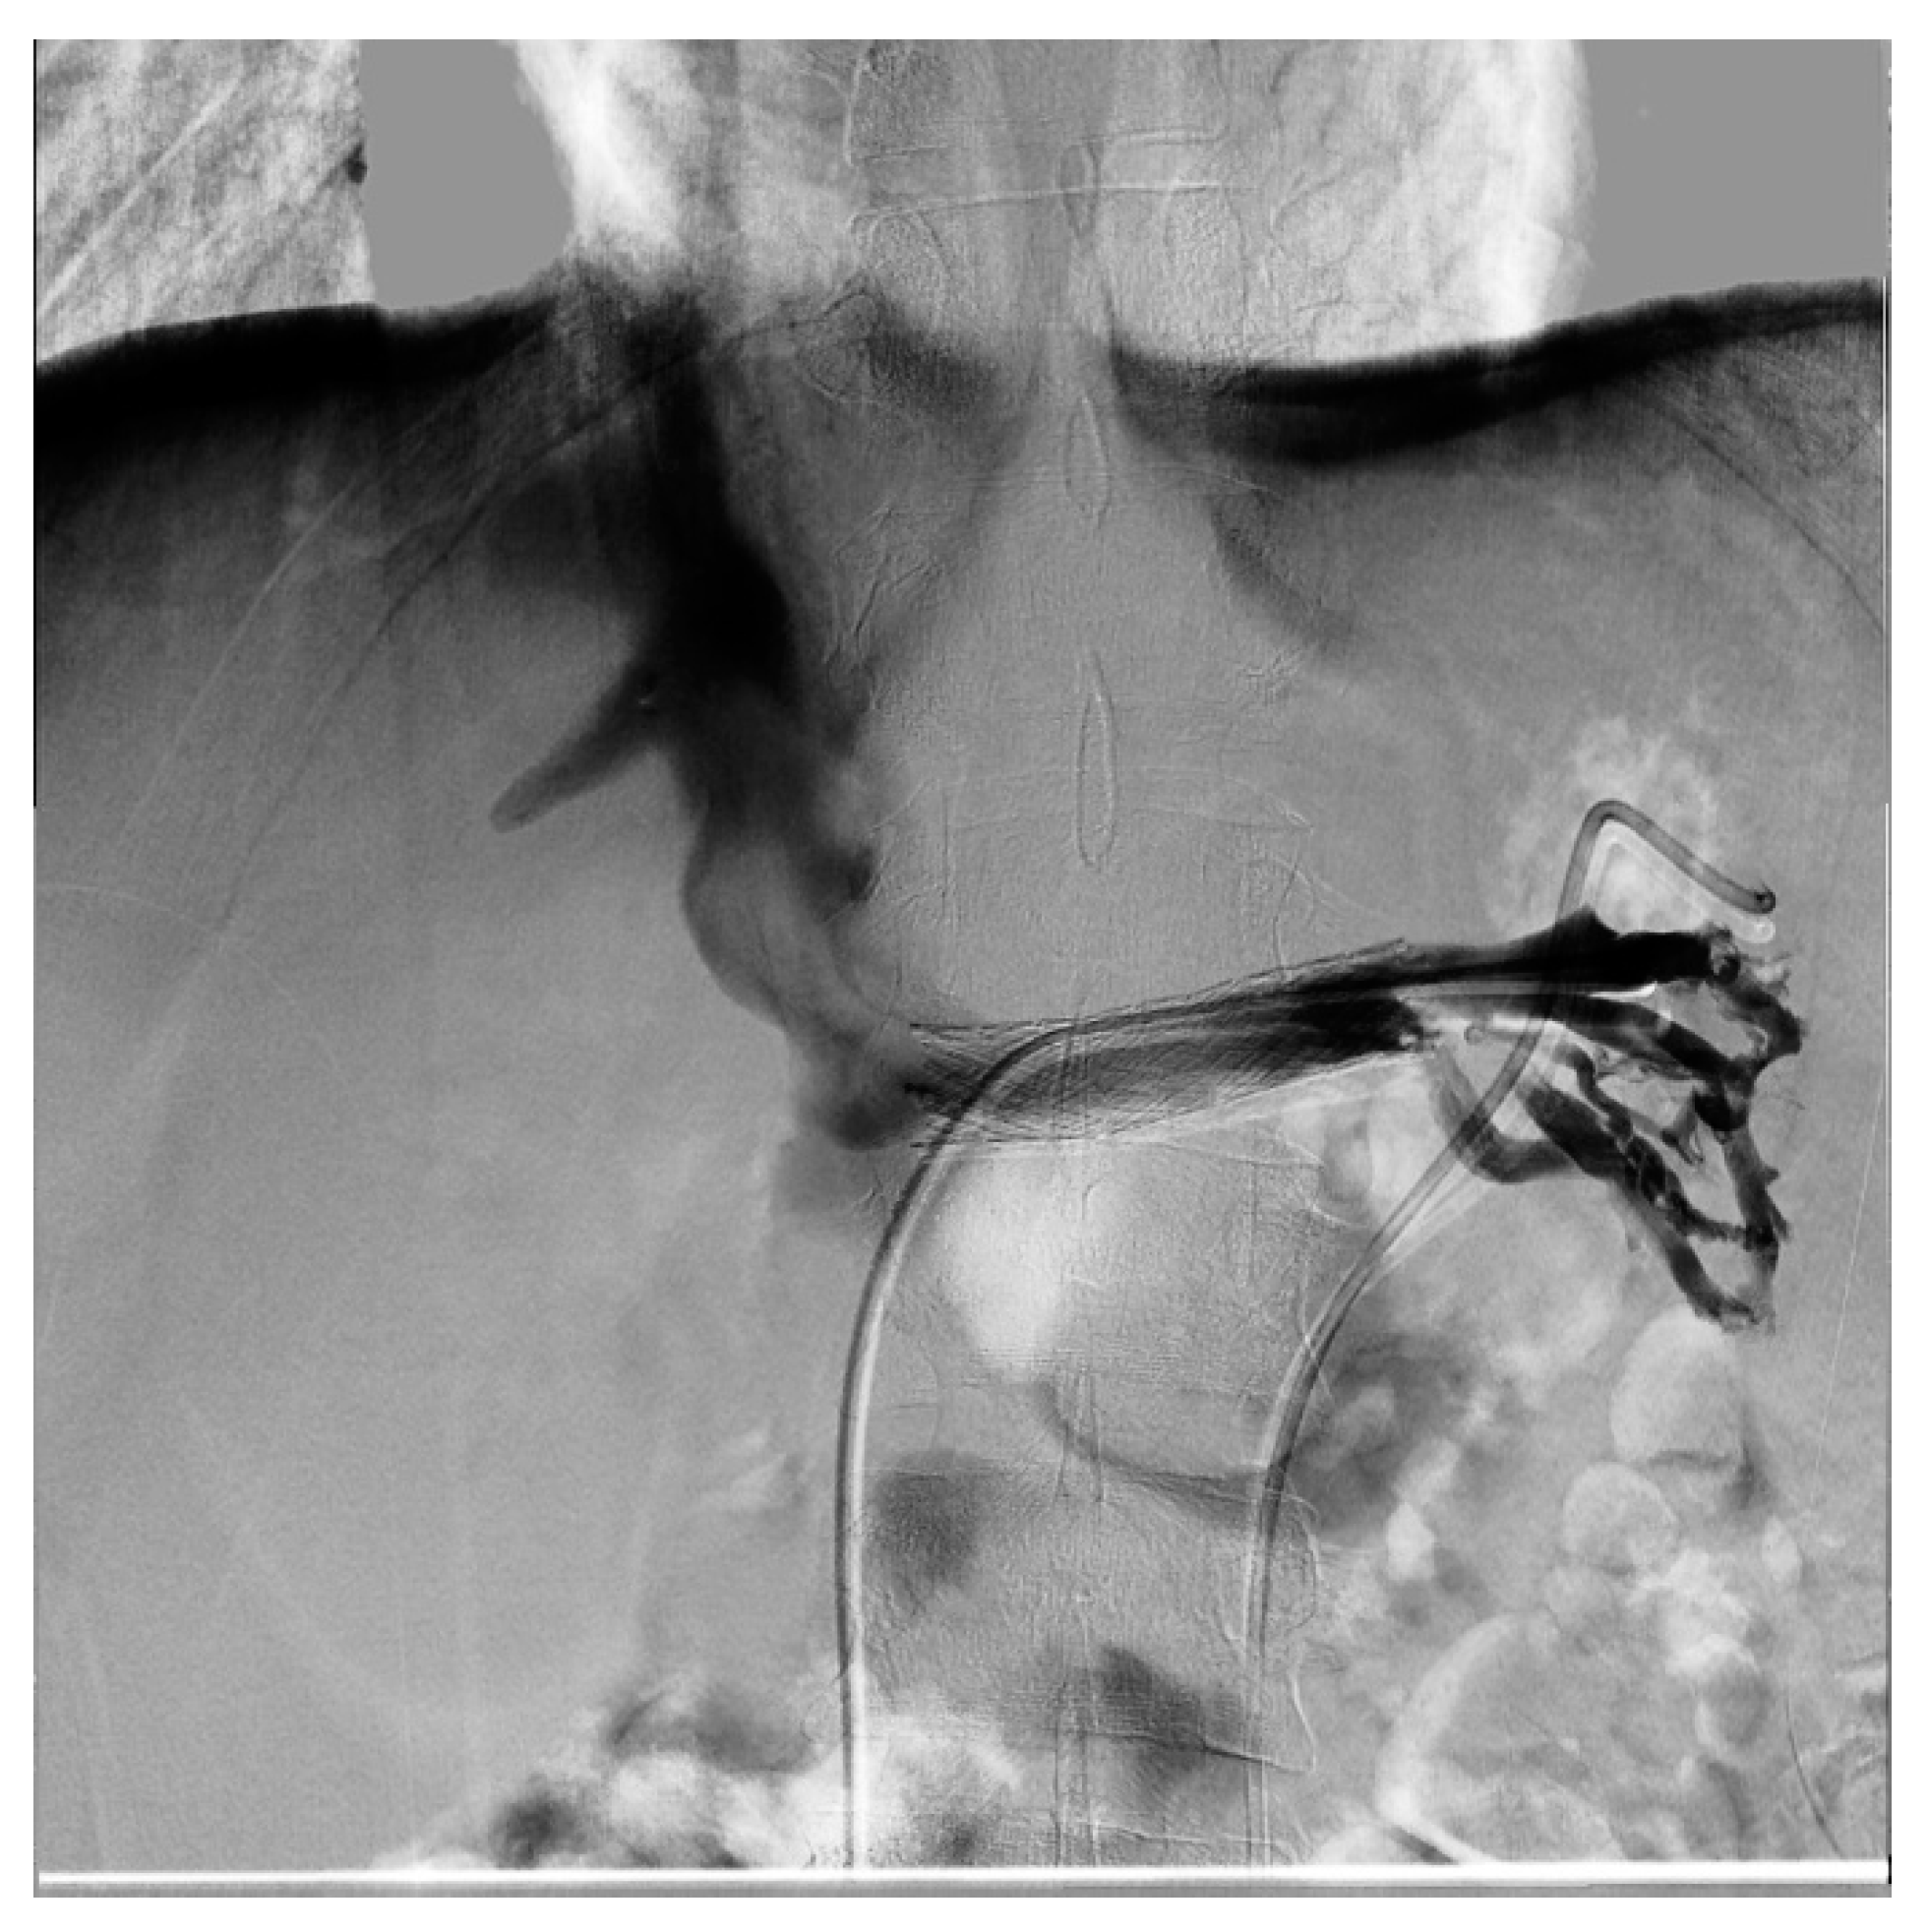

From Nutcracker Phenomenon to Nutcracker Syndrome: A Pictorial Review